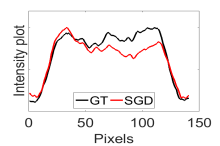

The calculated correlation coefficient (), SNR, as well as CNR values for all tested methods in the synthetic phantom experiment are shown in Table II. As seen in Table II, the proposed NCBC method achieved the highest , CNR as well as SNR values when compared to that of other tested methods. Visual results from the bias-corrected DW-MR synthetic phantom data produced using different tested methods is shown in Fig. 2(c-i). It can be observed that the MCBC, LEMS, and proposed NCBC method were able to achieve the best level of bias correction when compared to the other tested methods. This is particularly apparent in the peripheral zone (PZ) of the prostate gland as highlighted using red ROIs in Fig. 2(a-i), where intensity inhomogeneities are still present to a significant degree in the bias-corrected phantom data produced using the LS, SCIC, SGD and BCFCM methods, while strong inhomogeneity correction performance is achieved using MCBC, LEMS, and the proposed NCBC method. Furthermore, it can be observed that NCBC exhibited minimal intensity inhomogeneities when compared with MCBC and LEMS, particularly in the area that is highlighted using Red ROIs. To better represent the outperforming of proposed NCBC method in terms of bias correction using synthetic phantom, the data intensity profiles corresponding to the drawn blue line in Fig. 3(a) are shown in Fig. 3(b) for uncorrected data (red color plot) versus ground truth data (black color plot) and in Fig. 3(c-i) for corrected data using different tested methods (red color plots) versus ground truth data (black color plots). As the intensity profiles of Fig. 3(b-i) show, NCBC method was resulted in an intensity profile with the most flatness and less amount of variation compared to the intensity profiles of uncorrected image as well as reconstructed images using other tested methods as such confirms the better performance of proposed NCBC method in terms of bias field correction.